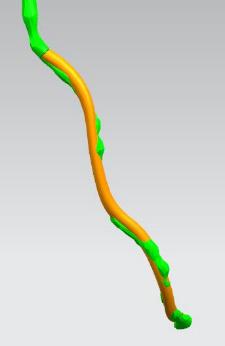

其次在对应的病灶位置进行一定的细节修改,或改变其形状或改变颜色以便于突出显示病灶位置。

模型细节修改

最后为方便医生观察病灶以及模拟手术,给整个冠脉模型添加支撑和底座,之后通过3D打印技术制作出来。

给冠脉模型添加支撑和底座并打印出来